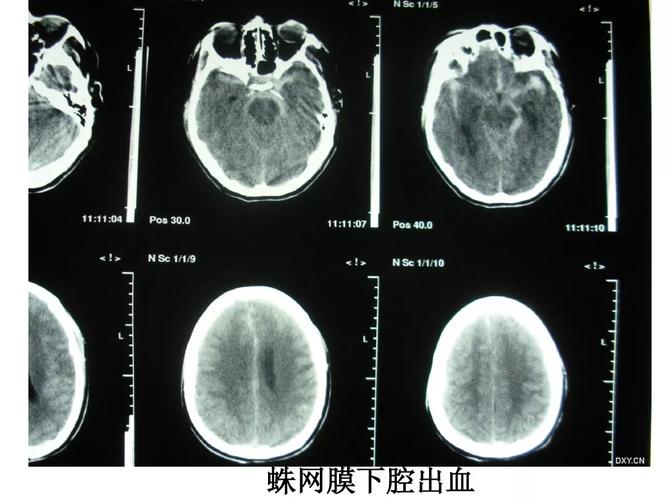

影像总结头颅ct基本知识与常见病变

脑部ct照片真实

脑出血头部ct图片

头颅CT图片